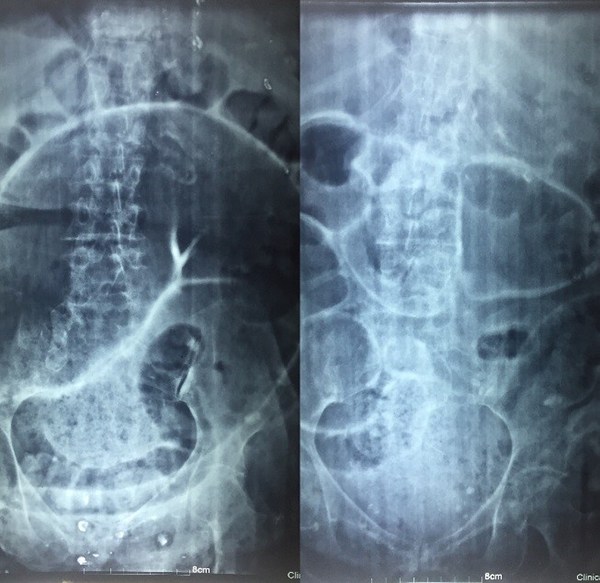

Son indicaciones: vólvulo del colon sigmoides recurrente (Fig. 1), pseudo-obstrucción, constipación funcional, incontinencia fecal y constipación crónica causada por afecciones neurológicas.

Figura 1: Mujer de 95 años con vólvulo recidivado del colon sigmoides.